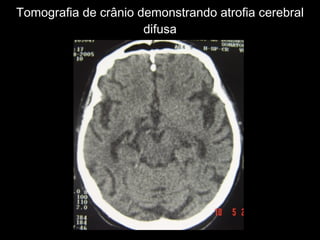

Tomografia de crânio demonstrando atrofia cerebral difusa

Tomografia de crâniodemonstrando atrofia cerebral difusa